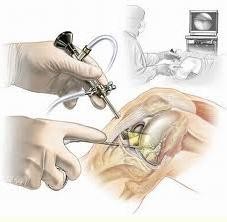

При неэффективности консервативных методов терапии прибегают к оперативному лечению. При относительно сохранной функции сустава и отсутствии контрактур возможно малое оперативное вмешательство: артроскопия. при помощи эндоскопической техники.

Какие операции колена осуществимы артроскопией?

• операция мениска

• пластическая операция передней поперечной связки

• вмешательство на хряще (заглаживание, пересадка тканей, и т. д.)

• удаление «суставных мышей»

• синовэктомия ревматоидного или воспалительного артрита

Через маленькие надрезы вводятся камерам инструменты, которыми манипулируют в суставной полости. На протяжении всего вмешательства обеспечивается циркуляция физиологической жидкости для того, чтобы гарантировать оптимальное качество изображения на видеоэкране.

Вот такие изображения можно наблюдать во время артроскопии колена :

Сустав промывают, извлекают разрушенные фрагменты хряща, менисков, удаляют остеофиты. Эта операция паллиативная, но она при малой травматичности позволяет улучшить функцию сустава на 2-3 года. Если обнаруживается преимущественное поражение внутренней или наружной части сустава, при небольших искривлениях голени, возможно выполнение операции под названием корригирующая вальгизирующая подмыщелковая остеотомия болыиеберцовой кости при поражении внутреннего отдела коленного сустава.